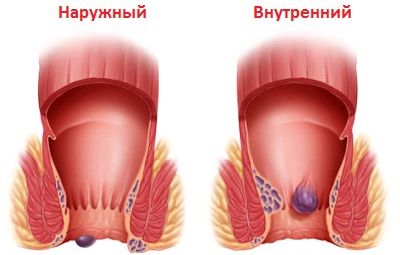

розрізняють зовнішній і внутрішній геморой. На численних фото можна побачити, як виглядає це захворювання зовні.

Загальний вигляд зовнішнього і внутрішнього геморою